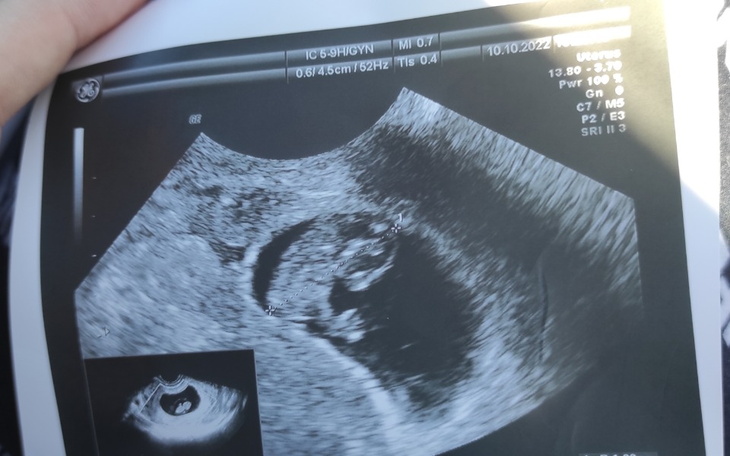

Mam na imię Maja i w maju przyszłego roku zostanę po raz pierwszy mamą. Ciąża była dla mnie zaskoczeniem, ale po pierwszym szoku i pierwszym usg pokochałam od razu tą małą fasolkę, która we mnie mieszka.

Ze względu na to, że w mojej rodzinie zdarzały się przypadki chorób genetycznych u dzieci mój ginekolog prowadzący ciążę zalecił mi wykonanie badań prenatalnych pierwszego trymestru. Niestety nie są one refundowane w moim przypadku. Na ten moment jestem już w 11 tygodniu ciąży a z badaniami prenatalnymi muszę zdążyć do końca 13 tygodnia ciąży. Termin badania umówiony na 10 listopada.